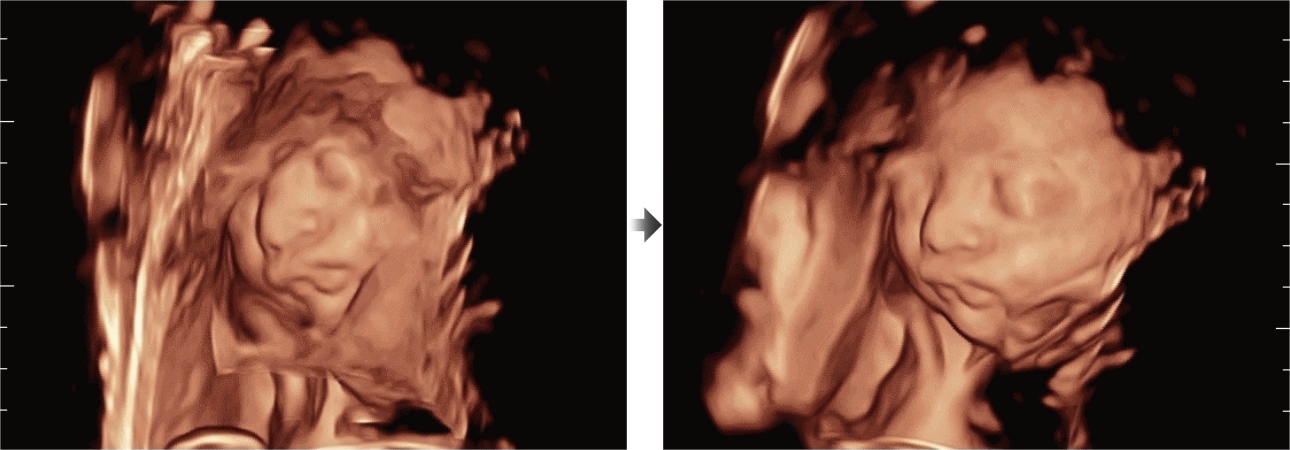

Naast de hoogwaardige beeldvormingskwaliteit verbetert de Resona 7 tevens de klinische onderzoeksmogelijkheden met de revolutionaire V Flow voor vasculaire hemodynamische evaluatie, en de intelligentste vlakacquisitie van een 3D-gegevenssets voor de diagnose van het foetale, centrale zenuwstelsel. Met zijn combinatie van de meest intu?tieve, op vingerbewegingen gebaseerde multi-aanrakingsbediening en alle essenti?le klinische functies loopt de Resona 7 voorop in de nieuwe golven van ultrasoundinnovatie.